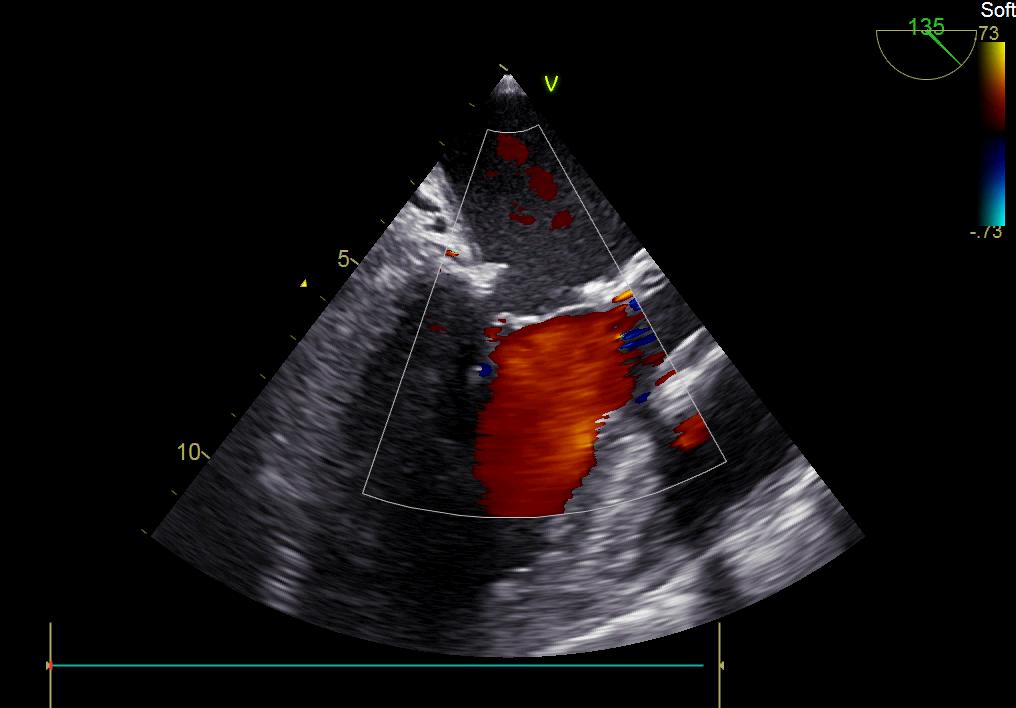

患者何某,42歲男性,因心功能不全入住我院心胸外科,心臟彩超提示二尖瓣后葉脫垂伴有重度返流及心臟擴(kuò)大,在迅速糾正心衰后,手術(shù)便提上日程,心胸外科廖金文主任多次組織全科及兄弟科室討論,在二尖瓣置換及成形術(shù)上,最終決定采取二尖瓣成形術(shù)。為保證手術(shù)安全,討論圍手術(shù)期各個(gè)細(xì)節(jié),所謂細(xì)節(jié)決定成敗,因?yàn)樾g(shù)前的細(xì)致全面,加上術(shù)中的一絲不茍及術(shù)后的精細(xì)化管理,患者術(shù)后恢復(fù)順利,健康出院,復(fù)查心臟彩超未見二尖瓣返流。

術(shù)后彩超